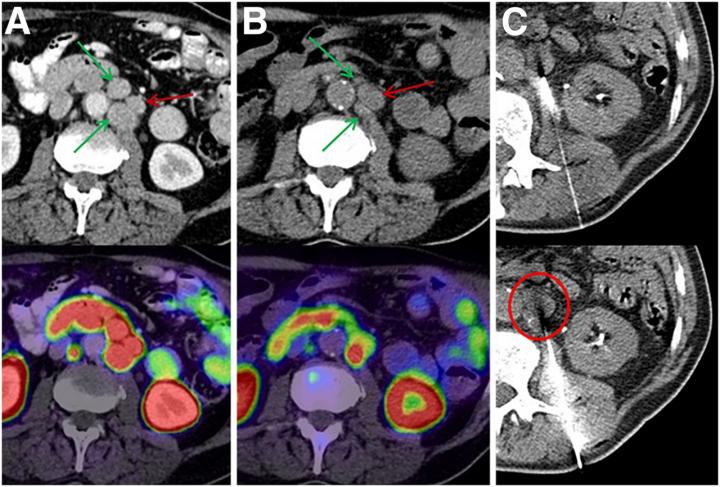

image: Intra-patient tumor heterogeneity makes tissue sampling of the most appropriate index lesion challenging. (A) Baseline PSMA PET/CT demonstrated group of 3 lymph nodes with homogeneously intense uptake with SUVs of 29.7-35.5 (arrows). (B) After 225Ac-PSMA therapy, 2 lesions with SUVs of 29.7 and 32.0 showed morphologic response (green arrows), but index lesion with highest initial uptake (SUV, 35.5) had increased size (red arrow) and persisting PSMA uptake (SUV, 30.0). (C) This lesion (encircled) was chosen for imaging-guided biopsy.

Images created by C Kratochwil and CP Heussel et al., University Hospital Heidelberg, Germany.